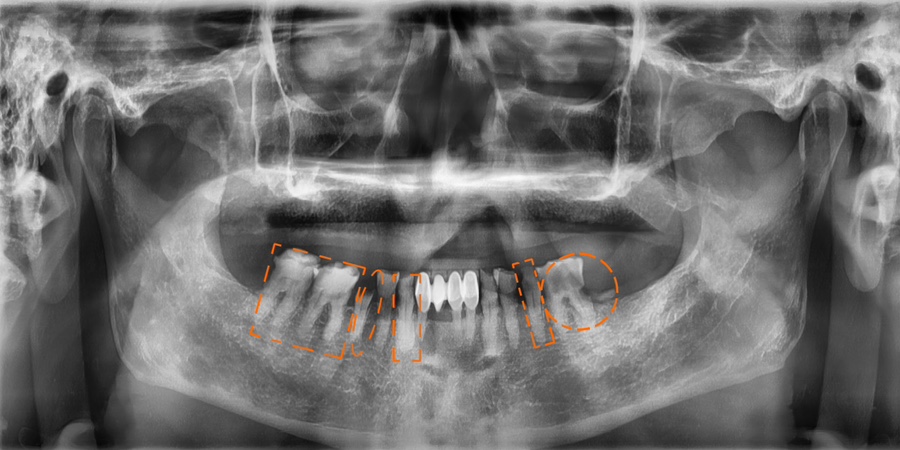

치료 전 사진 / 2024. 12. 18

치료 전 구강 상태 분석이 중요한 이유

치과 치료를 시작하기 전에는 현재 구강 상태를 정확히 파악하는 것이 중요합니다.

파노라마 엑스레이 등을 통해 치아, 잇몸뼈, 염증 여부를 확인하면 단순 치료인지, 임플란트나 발치가 필요한지 판단할 수 있습니다.

특히 치주염이나 치아 손상이 심한 경우에는 보존이 어려워질 수 있고, 치아 상실을 방치하면 뼈가 흡수되어 치료가 더 복잡해질 수 있습니다.

따라서 정확한 진단을 바탕으로 적절한 치료 계획을 세우는 것이 무엇보다 중요합니다.